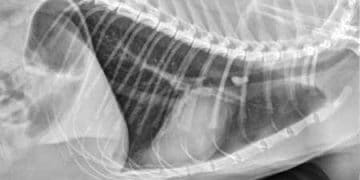

Yabancı Cisim Pnömonisi, fazla miktarda yabancı maddelerin özellikle sıvıların akciğerlere kaçması sonucu oluşan ve kangrenle sonuçlanabilen akciğer yangısına denir. Akciğerlere ...